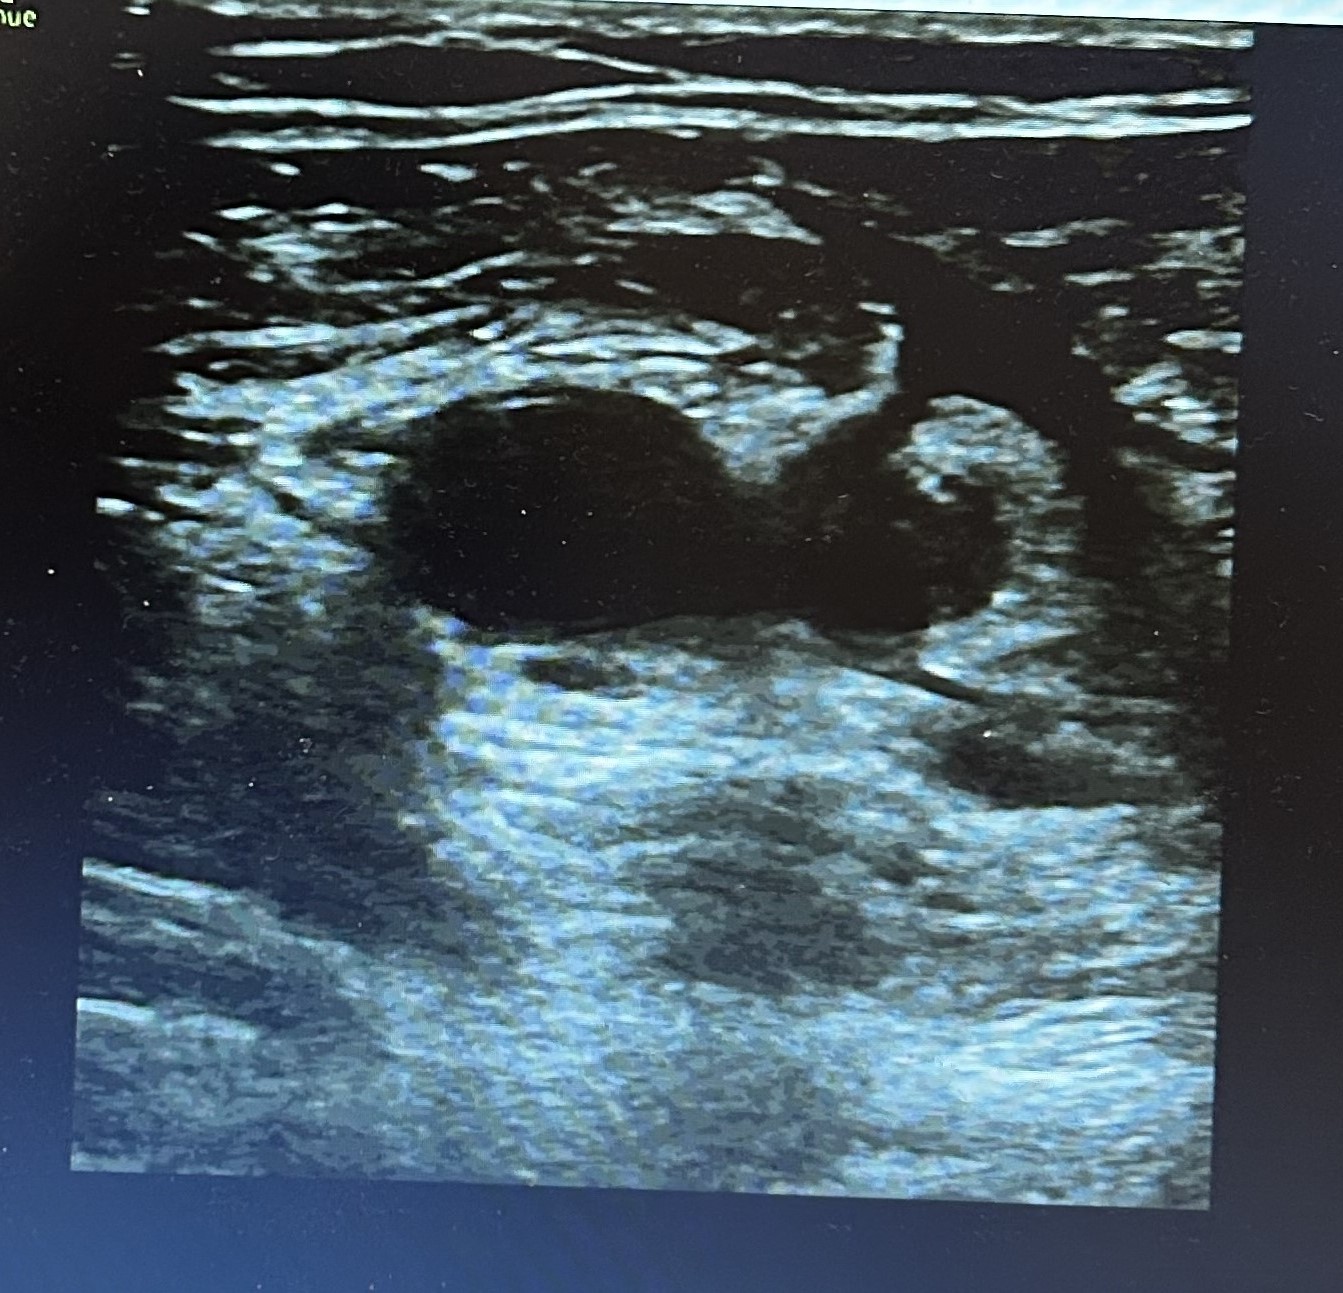

Ante cuadro sugerente de trombosis venosa se realiza ecografía-doppler venoso de la extremidad afectada objetivándose extensa Trombosis venosa profunda con afectación desde vena iliaca externa hasta territorio infrapoplíteo.